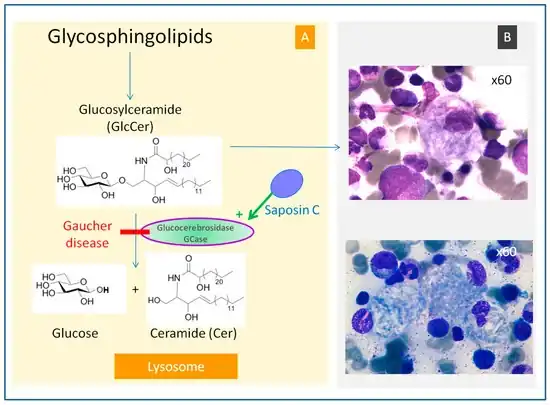

Gaucher's disease or Gaucher disease (/ɡoʊˈʃeɪ/) (GD) is a genetic disorder in which glucocerebroside (a sphingolipid, also known as glucosylceramide) accumulates in cells and certain organs. The disorder is characterized by bruising, fatigue, anemia, low blood platelet count and enlargement of the liver and spleen, and is caused by a hereditary deficiency of the enzyme glucocerebrosidase (also known as glucosylceramidase), which acts on glucocerebroside. When the enzyme is defective, glucocerebroside accumulates, particularly in white blood cells and especially in macrophages (mononuclear leukocytes). Glucocerebroside can collect in the spleen, liver, kidneys, lungs, brain, and bone marrow.

The disease is caused by a defect in housekeeping gene for lysosomal glucocerebrosidase (also known as beta-glucosidase, EC 3.2.1.45, PDB: 1OGS) on the first chromosome (1q22). The enzyme is a 55.6-kilodalton, 497-amino acid-long protein that catalyses the breakdown of glucocerebroside, a cell membrane constituent of red and white blood cells. In Gaucher disease, the enzyme is unable to function correctly and glucocerebroside accumulates. The macrophages that clear these cells are unable to eliminate the waste product, which accumulates in fibrils, and turn into 'Gaucher cells', which appear on light microscopy to resemble crumpled-up paper.[5]

A diagnosis can also be implied by biochemical abnormalities such as high alkaline phosphatase, angiotensin-converting enzyme, and immunoglobulin levels, or by cell analysis showing "crinkled paper" cytoplasm and glycolipid-laden macrophages.